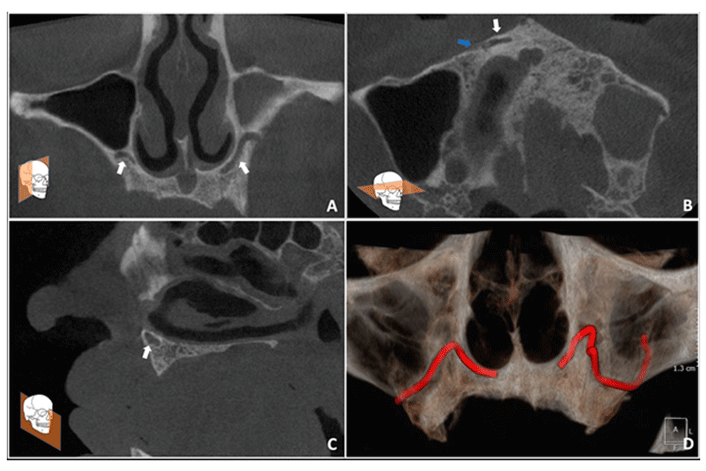

Canalis Sinuosus: An Anatomic Repair That May Prevent Success of Dental Implants in Anterior Maxilla

Canalis sinuosus (CS) is a neurovascular canal that corresponds to a small branch of the infraorbital canal. Although quite common, it is an often-overlooked anatomic structure that is not recognized by many dental practitioners and may be the cause of unintended injuries during dental procedures.

In this case report, the authors describe a case of a patient who suffered pain due to exposure of the CS, provide a review of other CS cases that were challenging to diagnose, and propose guidelines for preoperative examination of patients undergoing surgical procedures in the anterior maxilla.